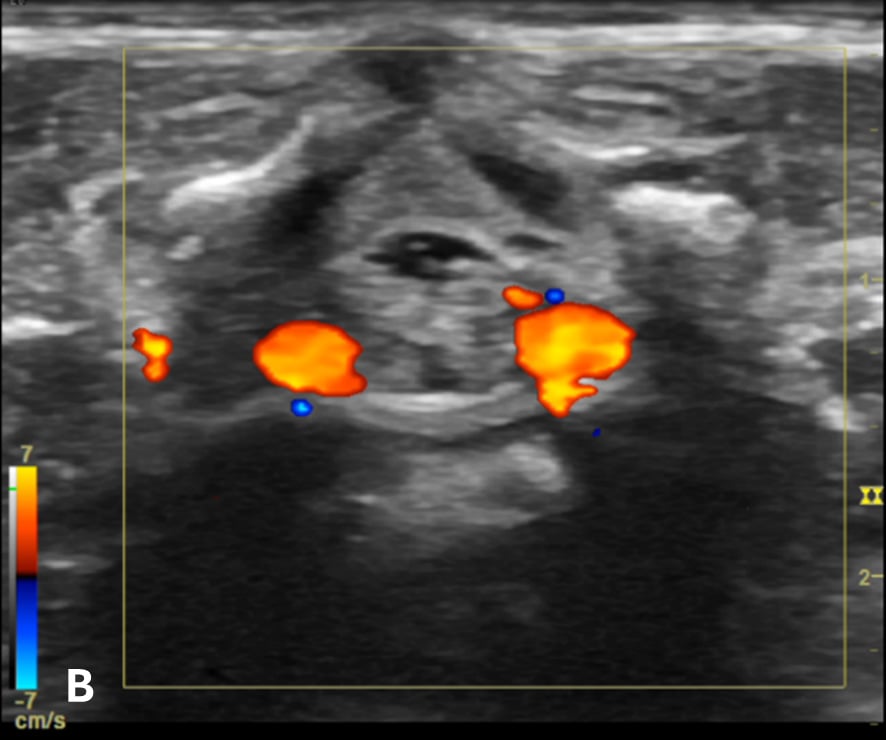

Figure 3 - Color Doppler US image of the spinal canal:

Figure 3B - The transverse view shows the anterior spinal blood vessels at the lateroventral part of the spinal canal.